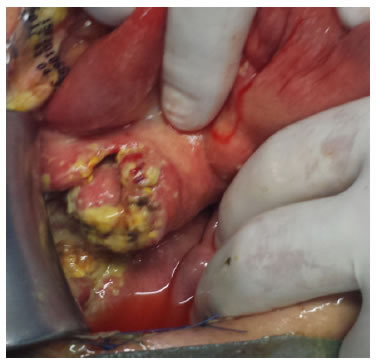

Durante la cirugía, se observó gran distensión de las asas intestinales delgadas, importante proceso de adherencias interasas, múltiples perforaciones a lo largo de todo el yeyuno, el íleon y el ciego, peritonitis fecal y múltiples ganglios con necrosis de caseificación en el mesenterio (figura 4). Se practicó una cirugía de control de daños para la sepsis de origen abdominal, con drenaje de la peritonitis fecal, resección de yeyuno distal, íleon y ciego, cierre temporal del colon ascendente, tres enterorrafias y yeyunostomía derivativa. Se requirieron 15 lavados quirúrgicos. Las fístulas intestinales originadas en las enterorrafias del yeyuno se trataron con sellador de fibrina, y se administró nutrición parenteral total y octreótido.

Las complicaciones incluyen obstrucción intestinal (31,7 %), perforación intestinal (4,9 %), fístula enterocutánea (2,4 %) y vólvulo intestinal secundario a la linfadenitis mesentérica (2,4 %), como las descritas en este caso.